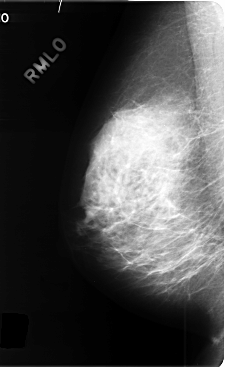

C_0358_1.RIGHT_MLO

LEFT_MLO LINES 4640 PIXELS_PER_LINE 2792 BITS_PER_PIXEL 12 RESOLUTION 50 OVERLAY

FILE: C_0358_1.LEFT_MLO.OVERLAY

TOTAL_ABNORMALITIES 1

ABNORMALITY 1

LESION_TYPE MASS SHAPE IRREGULAR MARGINS SPICULATED

ASSESSMENT 5

SUBTLETY 5

PATHOLOGY MALIGNANT

TOTAL_OUTLINES 1

BOUNDARY